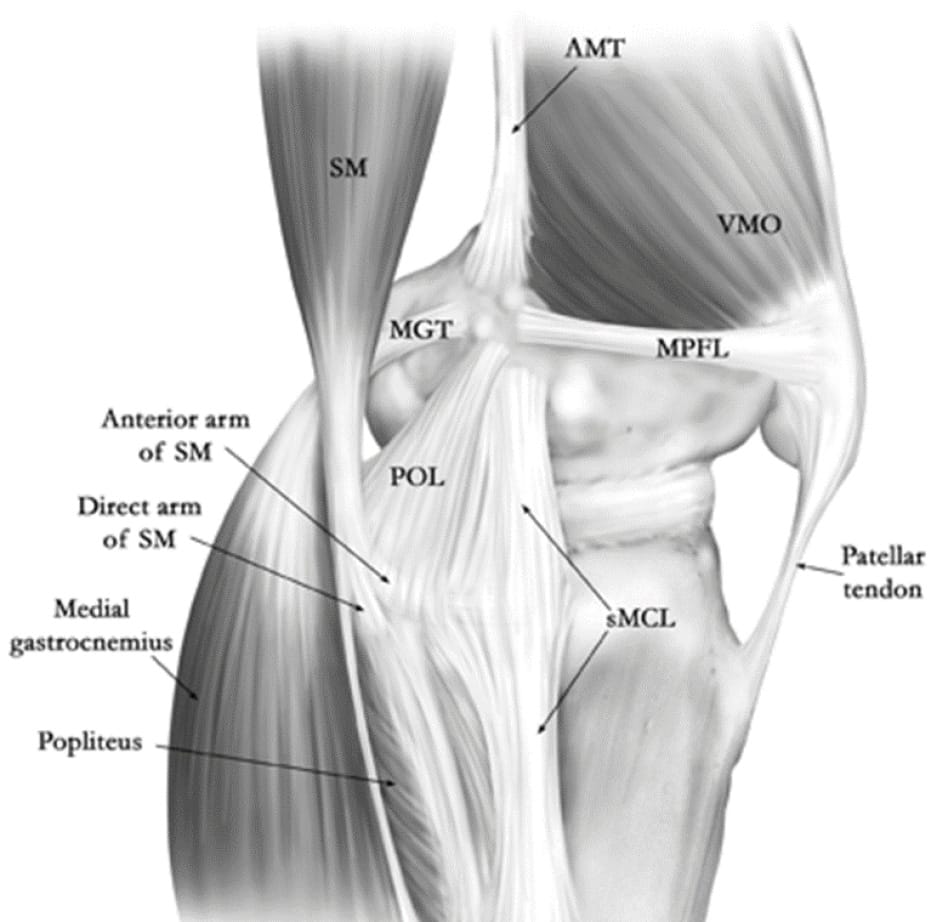

The medial side of the knee is made up of three distinct layers, described by Warren and Marshall (figure 1), that act as primary and secondary stabilisers of the knee, especially during valgus movements and rotation.

• Superficial layer: This consists of the fascia, sartorius and patellar retinaculum (Figure 2).

• Middle layer: This includes the superficial medial collateral ligament (sMCL), semimembranosus, semitendinosus, gracilis and posterior oblique ligament (POL). This ligament inserts over the medial epicondyle and terminates over the proximal tibia, 6cm below the joint line. It follows an oblique course down and forwards (Figure 3).

The POL forms the point of the posteromedial corner of the knee, together with the posteromedial joint capsule and the posterior horn of the medial meniscus. It inserts on the femur posteriorly and distally to the adductor tubercle. It ends at the semimembranosus tendon (at the anterior or reflected arm) (Figure 4).

• Deep layer: This layer includes the deep medial collateral ligament (dMCL), the joint capsule and the meniscotibial (or coronary) ligaments (Figure 5). The main role of the dMCL is to stabilise anterior translation and movements in valgus. It is made up of two parts: the meniscofemoral and meniscotibial ligaments. Its proximity to the joint capsule is worth noting as this explains the symptomatology of dMCL rupture, with the risk of joint stiffness in flexion.